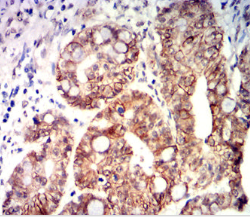

CDX2 Mouse Monoclonal antibody[5B4C1]

IHC    1/200-1/1000